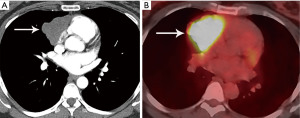

Thymic carcinoma and neuroendocrine tumor/carcinoid

Thymic carcinoma and thymic neuroendocrine tumors have similar imaging characteristics which may often overlap with the more aggressive histologies of thymoma, such as B3 thymoma. Thymic carcinomas and neuroendocrine tumors commonly present as large prevascular masses with irregular or poorly marginated borders, areas of necrosis or cystic change, and hemorrhage. Compared with thymomas, there is a greater incidence of local invasion (1) (Figures 2,11). Pleural or pericardial nodules, pleural effusion, and distant metastasis are more commonly seen with thymic carcinoma or thymic neuroendocrine tumor than thymoma (Figure 12). More aggressive thymic epithelial tumors can invade or compress the SVC resulting in SVC syndrome. This is a clinical syndrome marked by swelling of the neck, face, and upper extremities, with associated cough, headache, and shortness of breath. Pleural metastatic disease, which is more common in thymic carcinoma and thymic neuroendocrine carcinoma, generally consists of small enhancing pleural nodules or areas of enhancing pleural thickening. These are generally adequately assessed with thin-slice contrast-enhanced CT, although, contrast-enhanced MRI and PET/CT can be of additional benefit in questionable cases.

As noted, FDG PET/CT does not reliably differentiate between the different histological types of thymoma. Several small studies, however, have suggested that FDG PET/CT can help differentiate thymoma from thymic carcinoma using various cutoffs of SUV max ranging between 4.6 and 6.3 (49,50). Since the more aggressive tumor histologies are FDG avid, FDG PET/CT can be useful in the assessment and follow-up of thymic carcinoma but is not routinely recommended (51). Thymic neuroendocrine tumors can additionally be evaluated with 68Ga-DOTATATE PET/CT which may demonstrate improved sensitivity for lesion detection compared with FDG PET/CT which can help identify tumors that are candidates for peptide receptor radiotherapy (PRRT) with 177Lutetium (51).